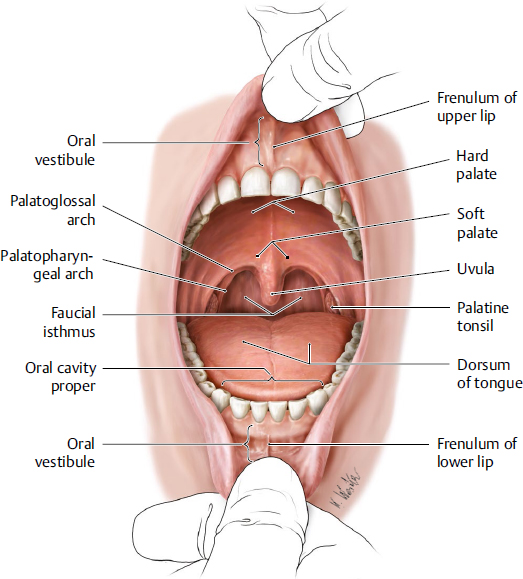

oropharynx: borders

oropharynx

from below the soft palate

to the tip of the epiglottis

oropharynx: how does it open into the mouth

via the oropharyngeal isthmus/ faucial isthmus

demarcated by the palatoglossal arch - anterior border of oropharynx

oropharynx: what does its lateral wall consist of

palatopharyngeal arch

palatine tonsil

tonsils: palatine tonsils location

palatine tonsils location

between the palatoglossal (anterior) and palatopharyngeal (posterior) arches

oropharynx